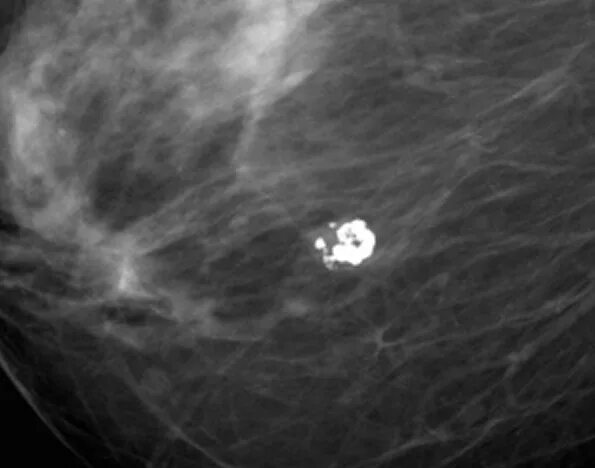

Выраженный диффузный фиброаденоматоз молочных